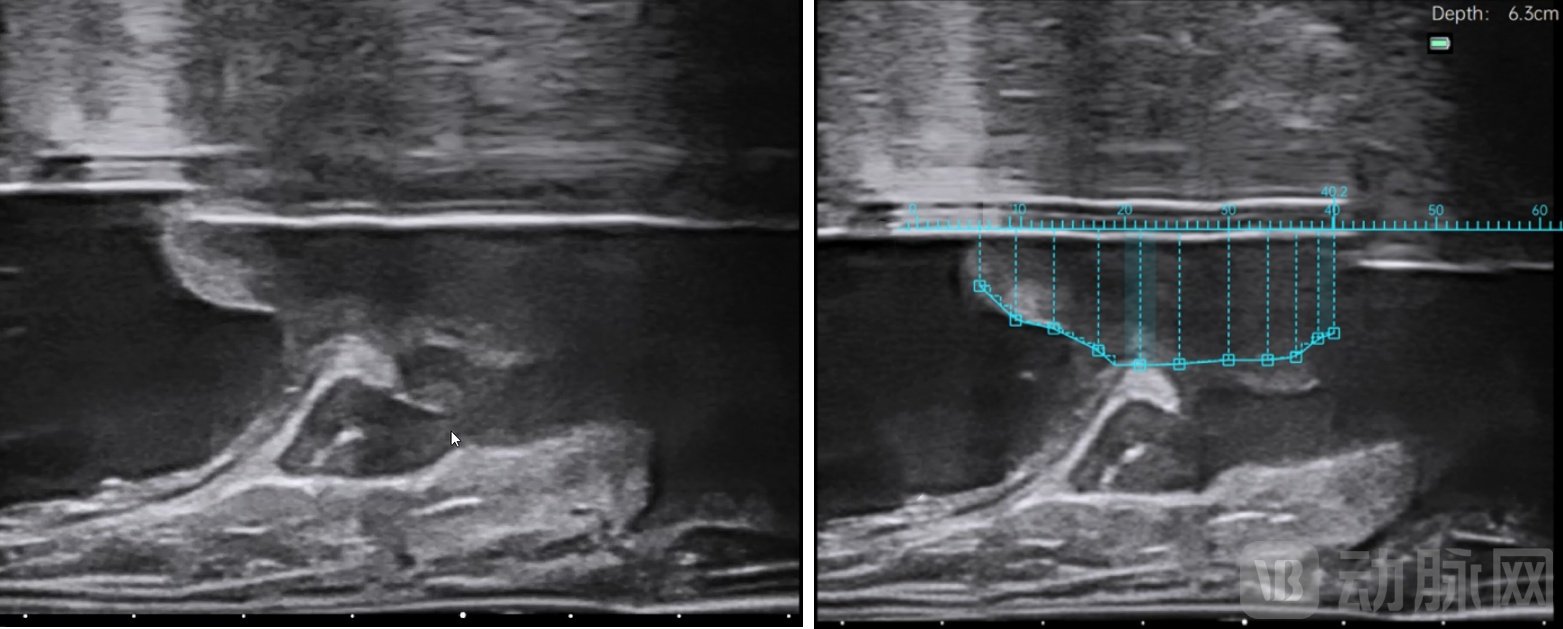

水刀机器人手术是第一个把智能影像术中超声影像引入到BPH手术中的术式。水刀手术机器人,也就是智能影像引导高能水射流自主手术机器人,会根据前期医生的在术中的全局规划,在影像导航的指引下,自动控制水刀精准切除。学习曲线短,对医生本身的经验和手术技巧要求较低,医生所要学习的就是如何通过影像规划手术靶区。由于水刀手术机器人是冷切割,从根本上避免了一切热损伤的可能性和各种各样的误操作,在保证有效性的基础上,更安全、更温和。

水刀手术机器人影像照片

在观察国外同类产品时,我们发现,它的产品在前期的患者数据采集和影像规划还是纯手工的方式,前期耗时较长,而且规划容易失准。所以我们把水刀手术机器人的器械设计成“全自动”的,把超声探头放在我们研发的自动采集数据装置上,这个装置会带着超声探头自动在直肠内扫描记录患者影像,给医生用于做整台手术规划。我们(的设备)只要进行一次自动的往复运动就可以完成整个数据采集,并用计算内容辅助医生完成手术整体规划。而国外同类产品的影像采集和规划还是纯手动的方式。如果你看过我们的主刀医生用水刀机器人做手术,会发现我们整个手术规划和执行过程,医生是在主控台前点鼠标或者踩下脚踏,器械的运动和切除不需要医生动手。